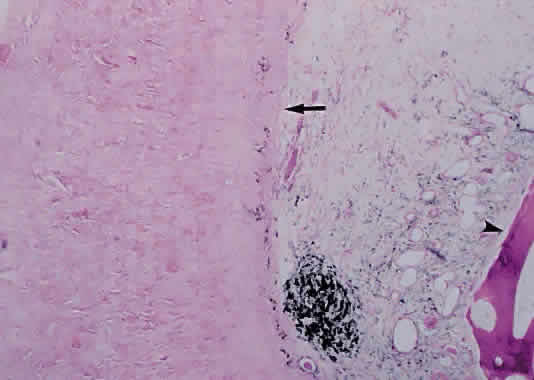

Much attention has been given to the histopathologic nature of the “snowbanks,” which has been studied by both light and electron microscopy.52,54,56–58 These fibrovascular-glial proliferations are found over the inferior pars plana and peripheral retina. They are composed of dense connective tissue derived from condensed, collapsed vitreous and often are vascularized. These vessels may reveal features of high endothelial venules (Fig. 8). Such endothelia are known to play a role in the homing of activated lymphocytes.54 The cellular elements of these membranes include fibroglial cells that are believed, based on their electron microscopic characteristics, to represent fibrous astrocytes, as well as nonpigmented ciliary epithelial cells, fibroblasts, and lymphocytes (Fig. 9).52–55,59,60 The vitreous is infiltrated by chronic inflammatory cells, and despite the nongranulomatous nature of the inflammatory component in the snowbanks, vitreous snowballs have been reported to consist of epithelioid cell granulomas.52

Fig. 9. A. Photomicrograph of “snowbank” in patient with pars planitis showing a fibroglial mass with proliferated epithelial elements (hematoxylin and eosin; × 31). B. Higher magnification showing epithelial elements and glial proliferation (hematoxylin and eosin; × 80). C. Chronic inflammatory cell infiltrate in pars planitis (hematoxylin and eosin; × 200).